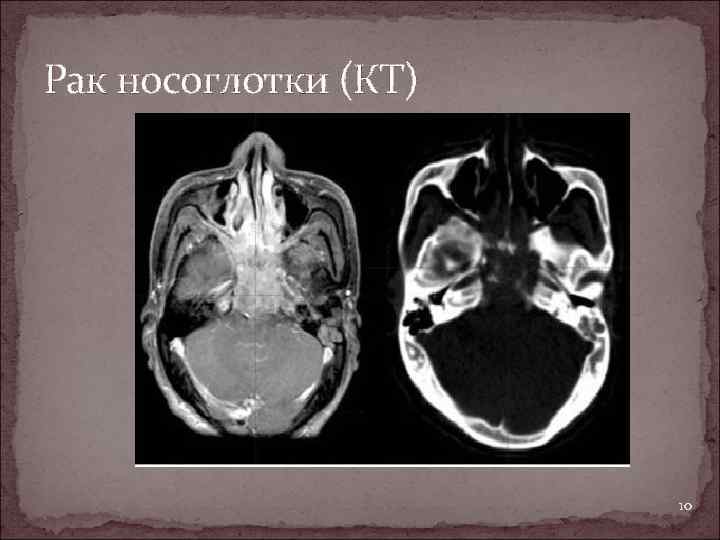

Рак носоглотки (КТ) 10